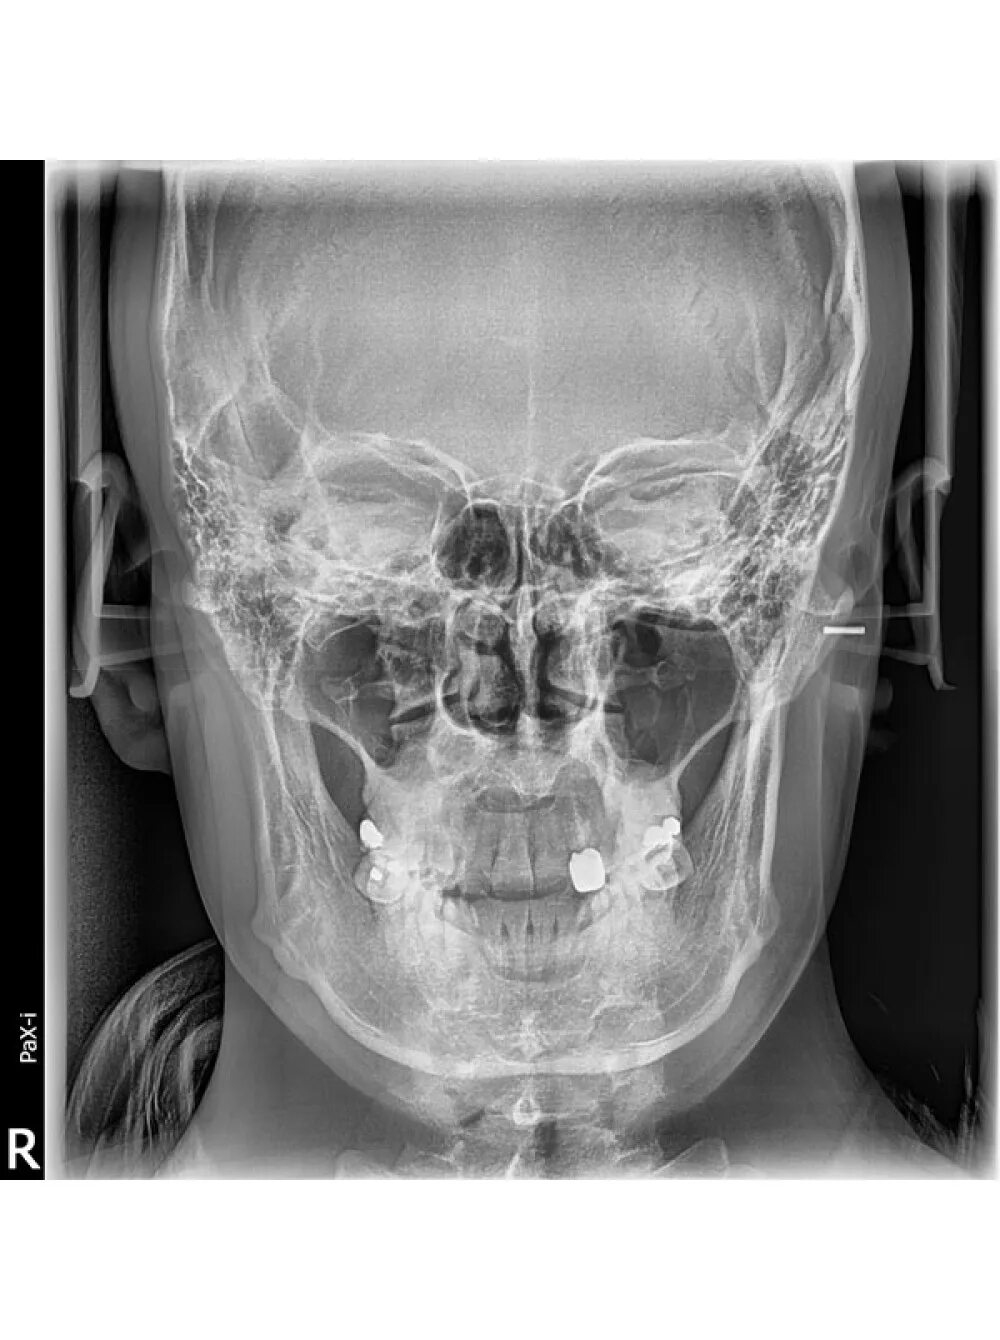

Снимок черепа в прямой проекции